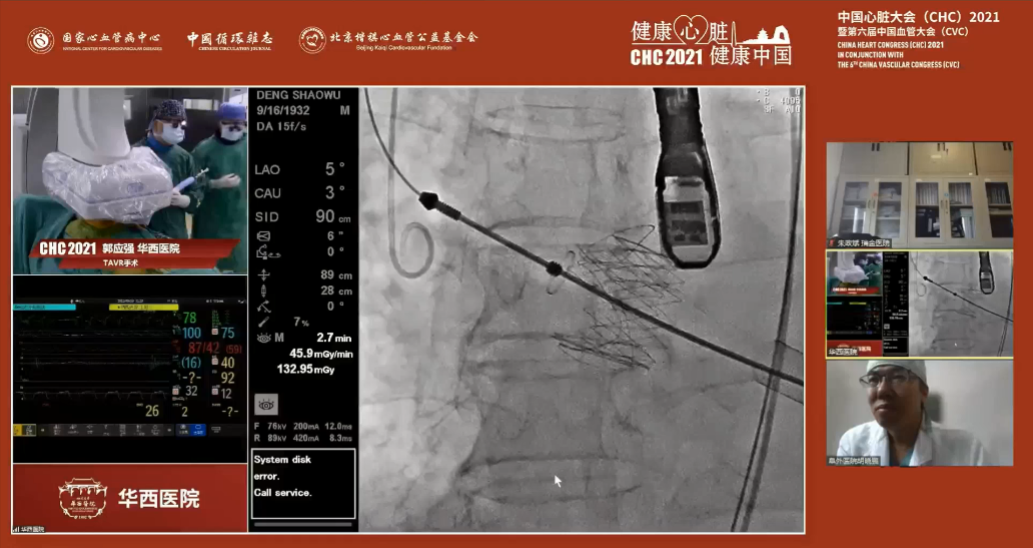

在2021年9月16日中国心脏大会(CHC)手术直播中,在全国结构性心脏病专家的共同见证下,来自四川大学华西医院心外科的郭应强教授团队成功挑战高难度“极度横位心”、单纯主动脉瓣重度关闭不全病例,同时也再次展现了J-Valve出众的性能。

4.患者术中造影角度LAO:5°,CAU:3°。

最佳投照角度:LAO:5°,CAU:3°

经右侧股静脉置入临时起搏器,经右侧股动脉在患者主动脉无冠窦内放置1根6F猪尾导管协助定位。透视下定位后第五肋间小切口进胸,打开心包,选择心尖裸区缝制六边形荷包。心尖穿刺后将泥鳅导丝过主动脉瓣经升主动脉、主动脉弓到达降主动脉膈肌水平(图1),通过TEE确认细导丝没有与二尖瓣腱索缠绕。单弯管交换硬导丝后(图2、图3),用16F扩张鞘预扩心尖穿刺处,后将 J-Valve瓣膜(29mm)装入输送器。将输送器推送至主动脉根部,释放定位件,适当调整定位件角度使其进入三个主动脉窦部,并通过DSA和TEE确定三个定位件准确入窦后完全释放瓣膜,撤出输送器(图4)。通过DSA和TEE观察人工瓣膜膨胀后金属支架的形态、位置良好,无瓣周漏,收缩期左室侧反流消失(图5、图6)。撤出导丝,收紧心尖处荷包线并打结,后鱼精蛋白中和肝素,彻底止血,逐层关胸,封皮,拔出股动脉鞘并在股动脉穿刺处压迫止血。手术过程顺利,患者生命体征平稳。

图1 超滑导丝进入左室、升主动脉内

图2 单弯管进入左室、升主动脉内

图3 主动脉瓣大量反流;主动脉瓣环平面几乎与脊柱平行

图4 释放定位件-定位件入窦-释放瓣膜-撤出输送器和单弯管